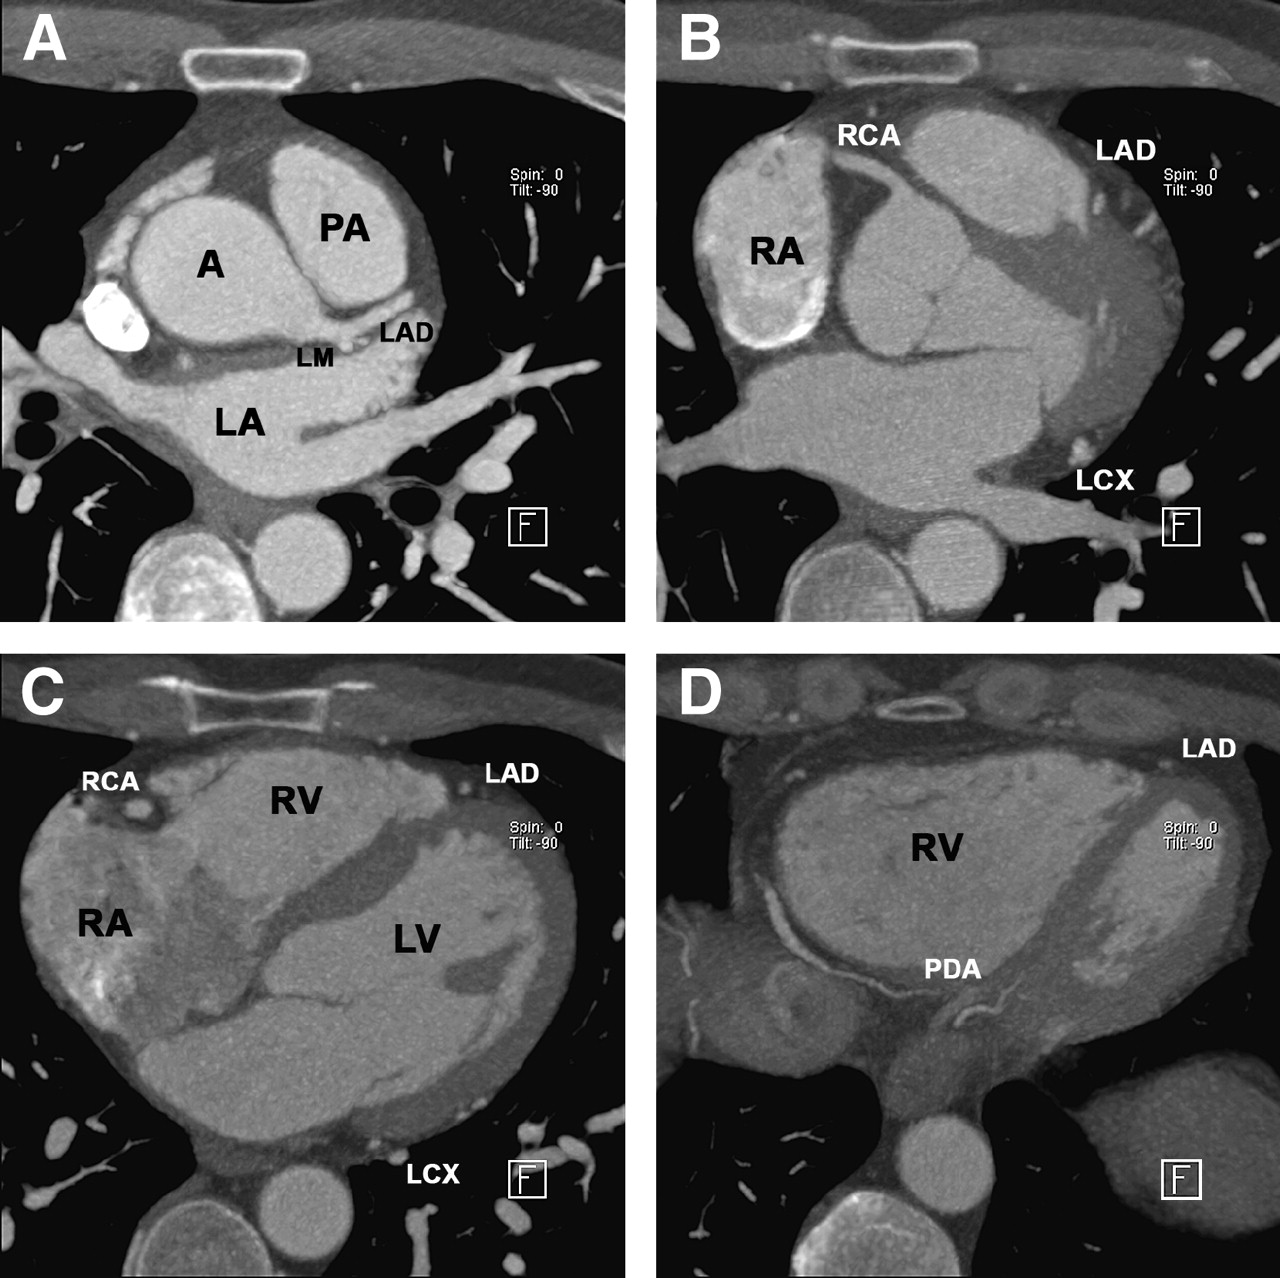

Cardiac CT